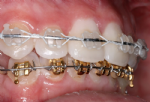

Behandlung mit weißen (zahnfarbenen) Brackets und goldenen Brackets

Die auf die Zähne geklebten Brackets sind in der Regel aus Stahl und daher silberfarbig. Stählerne Brackets sind besonders schlank und bieten eine sehr exakte Führung für die aktiven Elemente der Zahnspange. In manchen Fällen ist es auf Grund der beruflichen Situation des Patienten nötig, möglichst unauffällige, also zahnfarbene Brackets zu verwenden.

Auch die Verwendung goldfarbiger Brackets (und zum Teil auch Drähte) ist möglich und verbessert oft entscheidend die kosmetische Wirkung. Die Qualität derartiger goldfarbener Brackets ist dabei ähnlich gut wie die der silbernen.

Besonders elegant ist die Verwendung einer Kombination zahnfarbener und goldfarbiger Brackets.